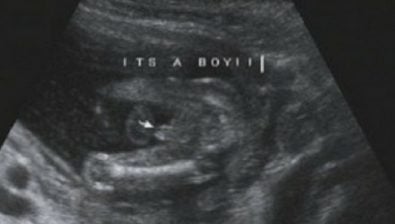

Ultrasound at 15 Weeks

Your baby has probably started to suck his/her thumb at this point. In fact, this action is often seen on ultrasounds. And, it’s super cute!